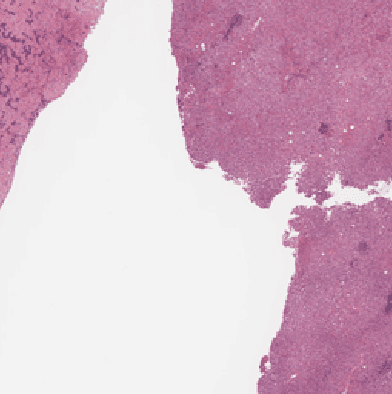

Recent breakthroughs in object detection and image classification using Convolutional Neural Networks (CNNs) are revolutionizing the state of the art in medical imaging, and microscopy in particular presents abundant opportunities for computer vision algorithms to assist medical professionals in diagnosis of diseases ranging from malaria to cancer. High resolution scans of microscopy slides called Whole Slide Images (WSIs) offer enough information for a cancer pathologist to come to a conclusion regarding cancer presence, subtype, and severity based on measurements of features within the slide image at multiple scales and resolutions. WSIs' extremely high resolutions and feature scales ranging from gross anatomical structures down to cell nuclei preclude the use of standard CNN models for object detection and classification, which have typically been designed for images with dimensions in the hundreds of pixels and with objects on the order of the size of the image itself. We explore parallel approaches based on Reinforcement Learning and Beam Search to learn to progressively zoom into the WSI to detect Regions of Interest (ROIs) in liver pathology slides containing one of two types of liver cancer, namely Hepatocellular Carcinoma (HCC) and Cholangiocarcinoma (CC). These ROIs can then be presented directly to the pathologist to aid in measurement and diagnosis or be used for automated classification of tumor subtype.